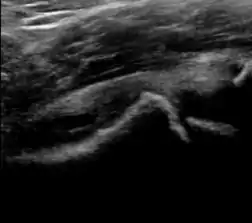

A step between the head and the physis can be detected in children with SCFE, while abnormalities in the femoral head contour may suggest the presence of LCPD. In both cases, radiographs are mandatory to confirm diagnosis and severity (Figure 12).[1]

Figure 12:

Step in the femoral head-neck junction in a patient with SCFE.